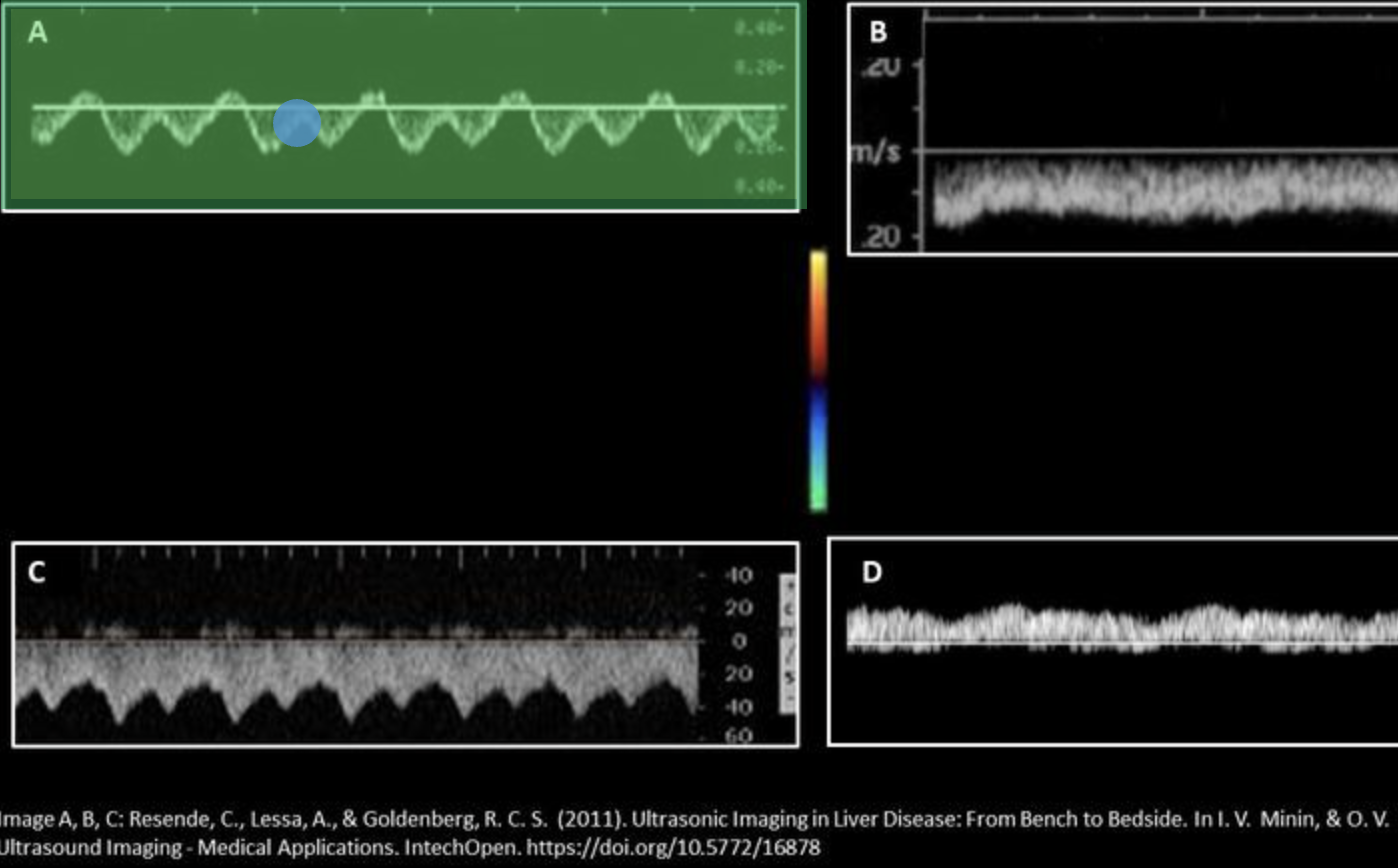

Which waveform represents a normal portal vein waveform? Use your mouse to position your cursor over the correct waveform and click to set the answer.

***the color map displayed applies to all displayed Doppler tracings.

Normal hepatic venous flow will demonstrate:

Which waveform represents a normal inferior vena cava waveform? Use your mouse to position your cursor over the correct waveform and click to set the answer.

***the color map displayed applies to all displayed Doppler tracings.